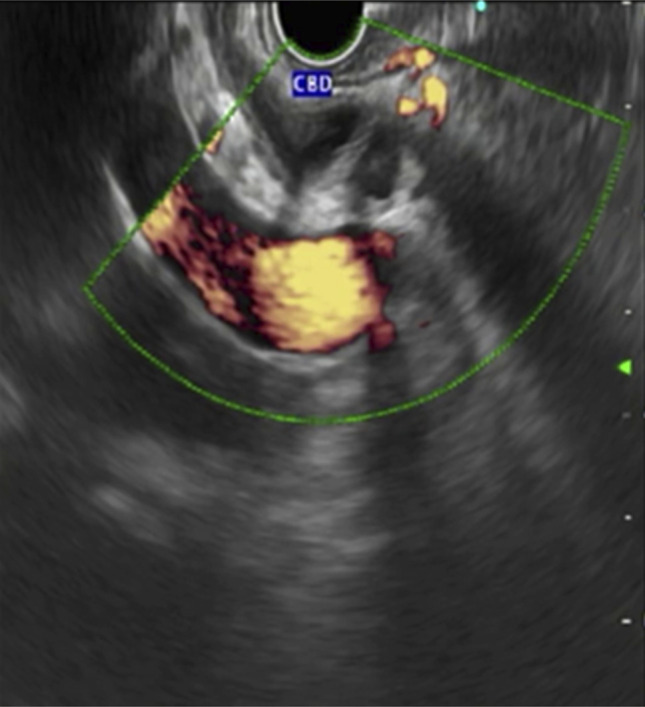

This is the first reported case demonstrating endoscopic ultrasound (EUS) findings in type Va duplication. The malformation of the congenital extrahepatic bile duct is classified as type Va and is rarely observed. To date, not more than 30 cases have been reported in Western literature. For the medical literature, a 50-year-old man with a type Va extrahepatic bile duct obstruction is examined. He presented with abdominal pain and jaundice, and imaging showed biliary dilatation and cholelithiasis. During the EUS procedure, an endoscopic examination revealed the presence of a duplicated common bile duct with a septum. Endoscopic retrograde cholangiopancreatography of the biliary tract also showed the same anomaly, with the presence of obstructive biliary sludge. The case highlights the need to consider EUS as a potent alternative diagnostic method. It is important to detect these anomalies immediately to reduce the chances of endoscopic/surgical complications.

Abstract Image